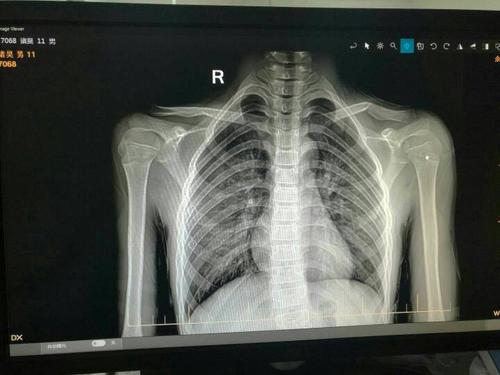

小孩锁骨骨折

11岁的,小孩锁骨断了,是保守治疗还是动手术?

儿童锁骨骨折图片

儿童锁骨青枝骨折图片

儿童锁骨骨折